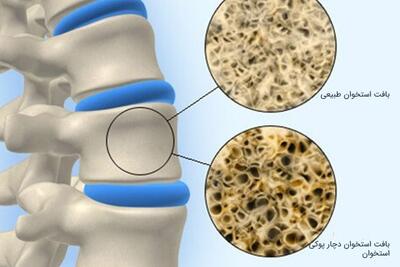

پوکی استخوان؛ بیماری خاموش، اما شایع در جامعه

زنان خانهدار و تهدید خاموش پوکی استخوان / ۴۰ درصد زنان ایرانی بالای ۶۰ سال به پوکی استخوان مبتلا هستند (فیلم)

نگرانکنندهتر آنکه سن بروز این بیماری در ایران ۱۰ سال زودتر از میانگین جهانی است. در این میان، زنان خانهدار، بیشتر در معرض خطرند؛ زنانی که با وجود انجام کارهای یدی مداوم، دسترسی منظم به خدمات پزشکی ندارند.